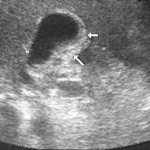

Толщина стенок органа не должна превышать 5 мм. Увеличение этого показателя указывает на наличие хронического воспалительного процесса. Также при уплотнении стенок отмечается изменение эхо-плотности контуров органа.

Увидев заключение ультразвукового исследования, пациенты начинают интересоваться вопросом: что значит уплотнение стенок желчного пузыря? Стоит отметить, что под этими словами подразумевается морфологическое изменение органа. Уплотнение стенок – это не самостоятельный диагноз. Данный симптом обнаруживают во время инструментального обследования. Этот признак практически всегда означает, что у пациента имеется хроническое воспаление желчного пузыря.

Диагностика болезней желчного пузыря

Признаки уплотнения стенок желчного пузыря относятся к показаниям для проведения диагностических процедур. К лабораторным особенностям хронического холецистита относятся: повышение АСТ и АЛТ. Уровень этих ферментов увеличивается при застое желчи в протоках. В период обострения отмечается лейкоцитоз и ускорение СОЭ в анализе крови.

Помимо УЗИ проводится компьютерная томография брюшной полости, рентгенография. В некоторых случаях требуются специальные инвазивные исследования. Среди них – ретроградная холангиопанкреатография.